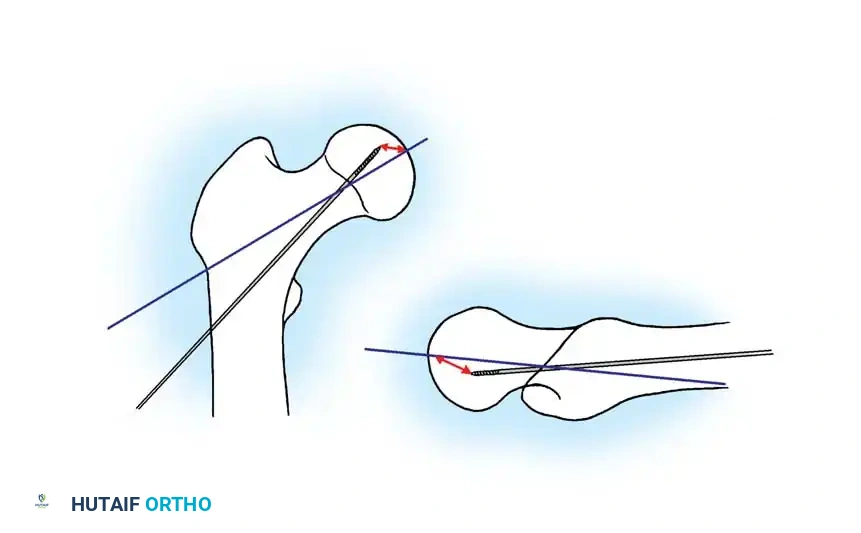

3. Guide Wire Placement

Whether using an SHS or a CMN, accurate placement of the guide wire into the femoral head is the most critical step of the operation.

Insertion of the guide wire. The wire must be positioned centrally in the femoral head on both AP and lateral views.

The Tip-Apex Distance (TAD):

Described by Baumgaertner, the TAD is the sum of the distance from the tip of the lag screw to the apex of the femoral head on both the AP and lateral radiographs. A TAD of less than 25 mm is strongly predictive of successful fixation; a TAD > 25 mm significantly increases the risk of screw cut-out.